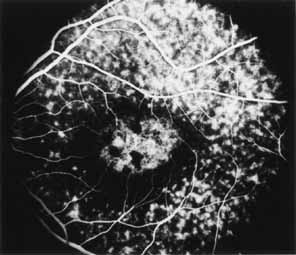

Although there is no reported genetic heterogeneity, there is wide phenotypic variation within the disorder. The major finding within the macula is a classic radial cystic maculopathy. Although retinal signs have been described in infants as young as 3 months, foveal schisis may be difficult to detect, leading to underdiagnosis. The diagnosis is usually not made until the affected male reaches school age (4 to 8 years of age) and encounters visual problems secondary to foveal involvement. Typical foveal schisis findings have been reported in 68% to 100% of eyes within various series.37,38 Foveal schisis is the only finding in about half the cases. It is characterized by the presence of radiate perifoveal microcysts located in the nerve fiber layer (Fig. 1) with radiate plications of the overlying internal limiting membrane that are seen especially well on monochromatic (red-free) photography (Fig. 2). The microcystoid change may slowly progress to form a macular cyst or hole. Foveal schisis has been reported in association with Goldmann-Favre vitreotapetoretinal dystrophy and rarely may be seen in rod-cone dystrophy or as an autosomal dominant or recessive condition.39–43

|